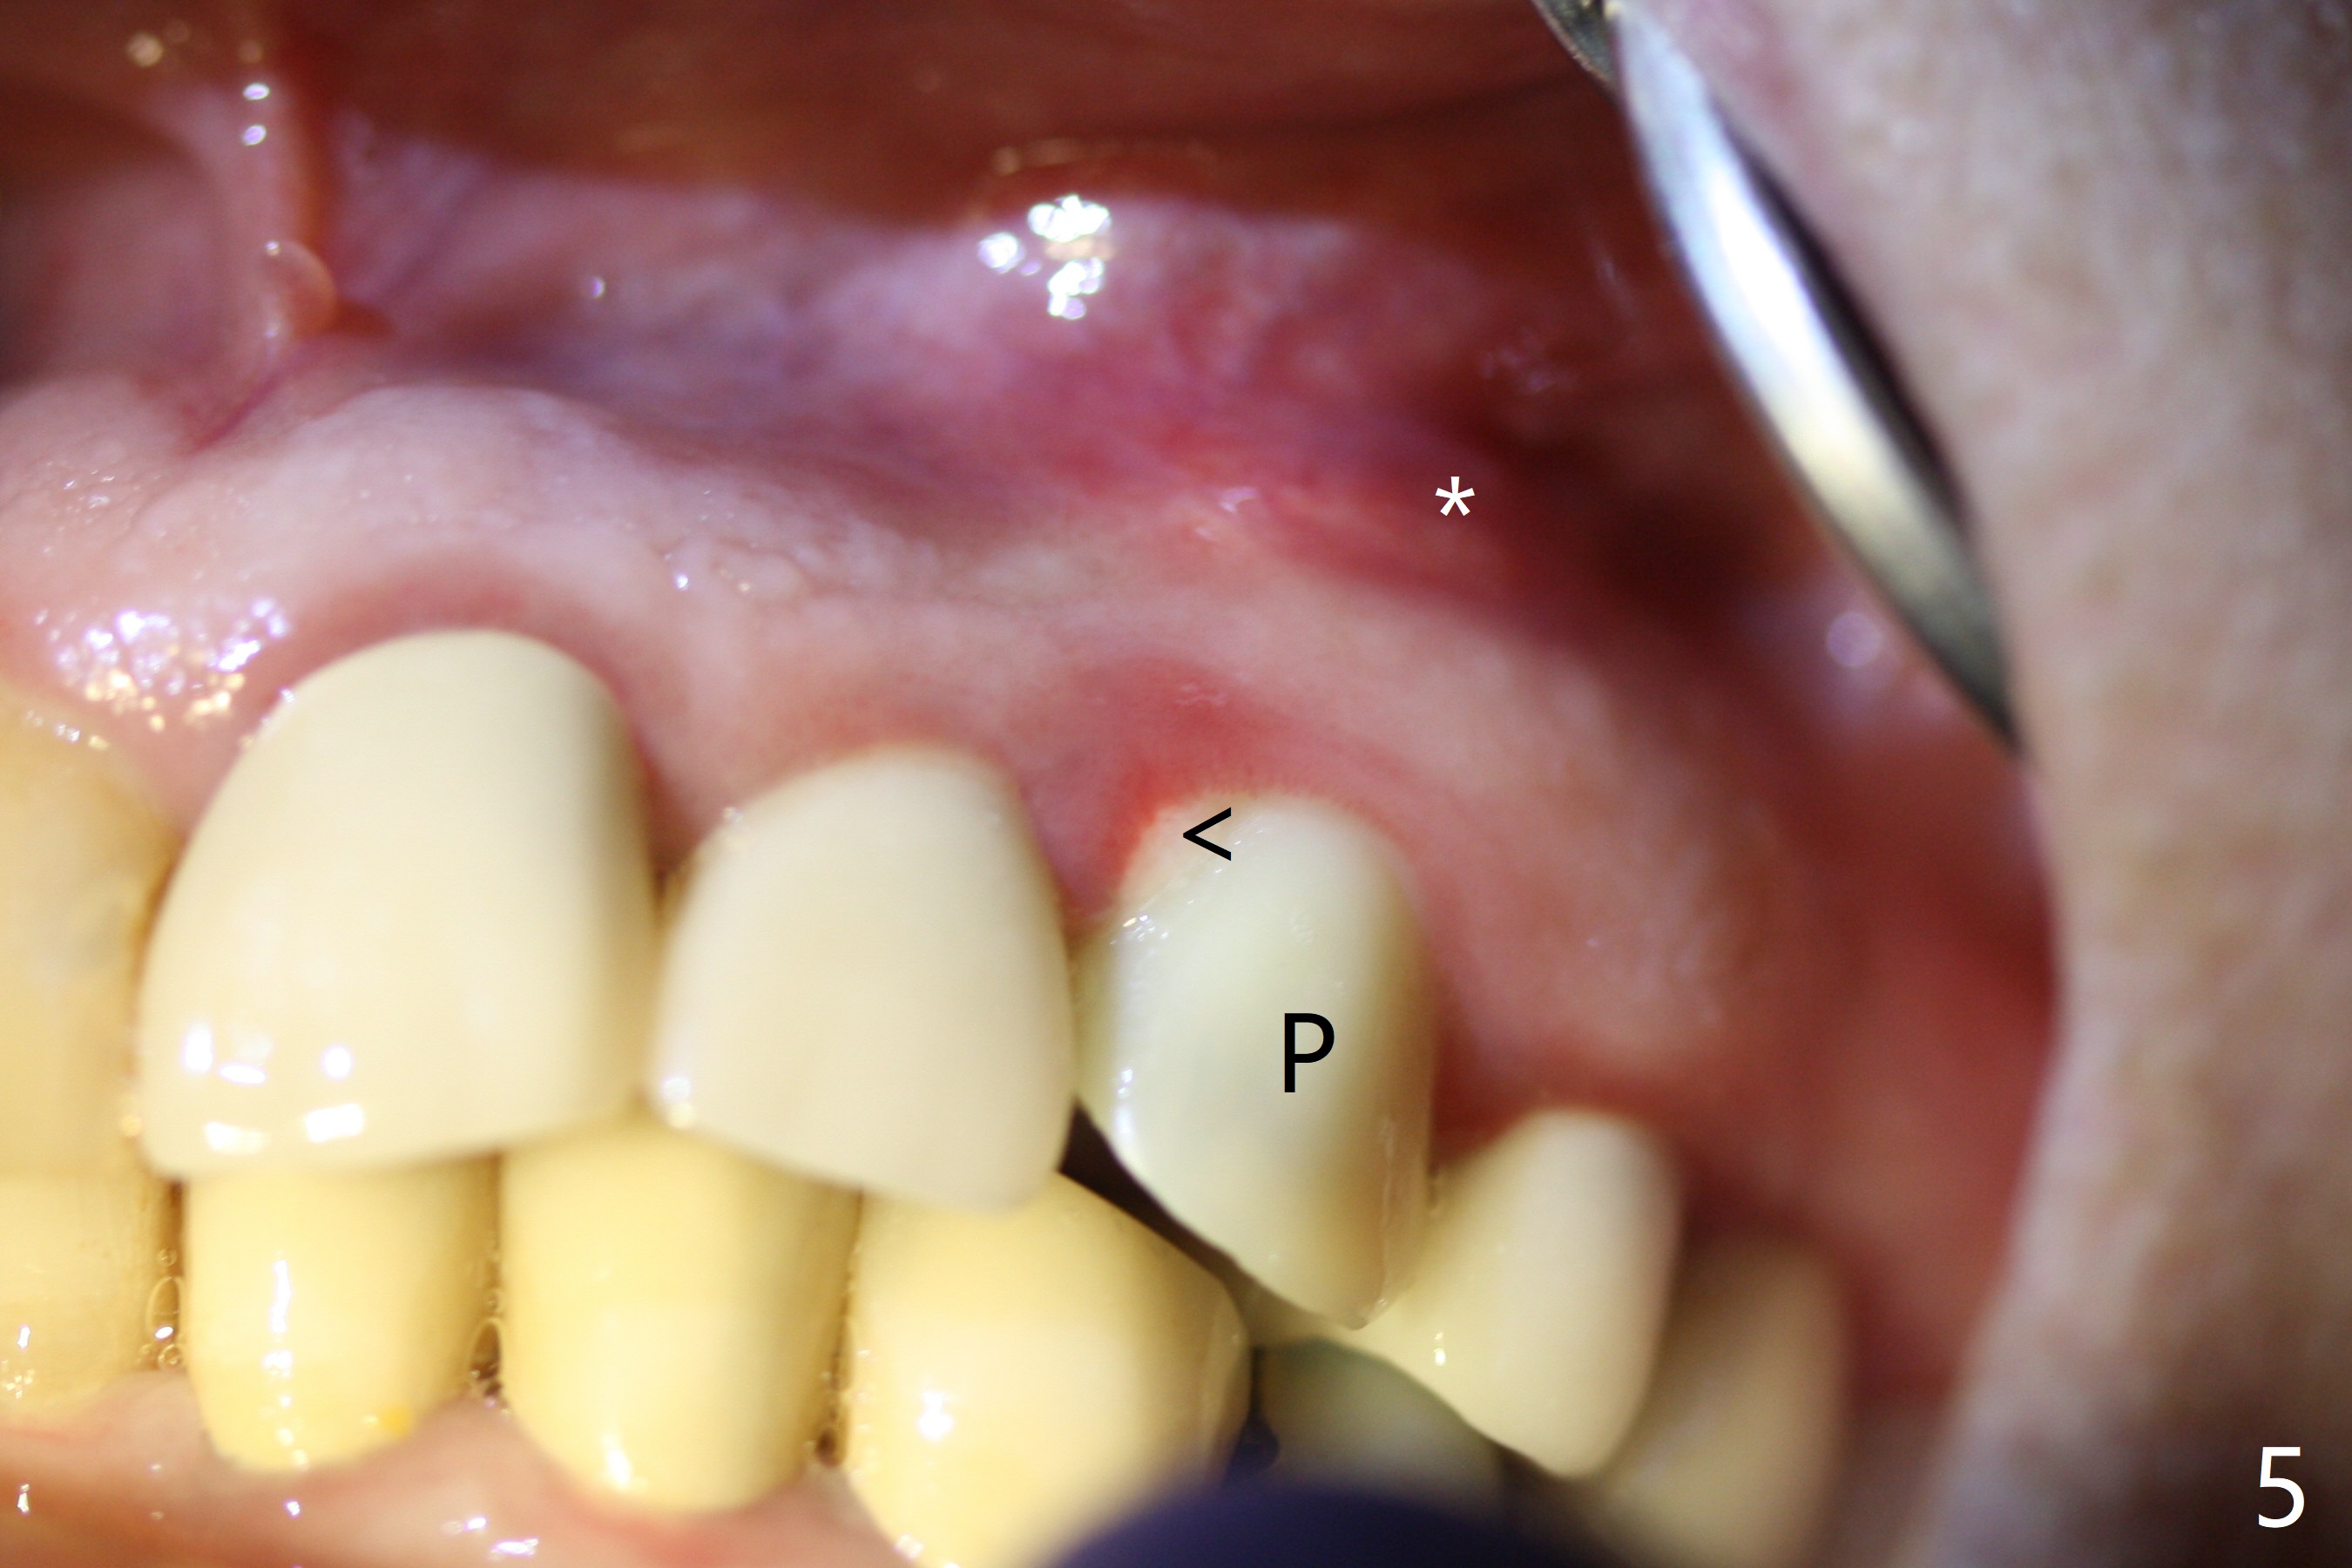

In spite of severe apical infection (Fig1,2 *), a thin narrow strip of the buccal plate (arrowheads, corresponding to the keratinized gingiva) is present when the tooth #11 is extracted. The thin bone keeps the bulging alveolus, i.e., reservoir for bone graft (Vanilla/Osteogen Fig.4 *) after placement of a 3.8x16 mm implant (Fig.3,4). A 4.5x1 mm temporary abutment, placed and trimmed for an immediate provisional, seems to be short in cuff. When an implant is placed deep to prevent periimplantitis, the cuff should be longer, i.e., 3 mm. X-ray should be taken for the depth confirmation after temporary abutment placement. Eight days postop, the mesial gingiva erythema has subsided (Fig.5 < (P: provisional)), while the apical swelling is no longer tender and most likely due to packed bone graft (*). Panoramic X-ray taken 2 weeks postop shows the clearance from the nasal cavity or the maxillary sinus (Fig.6). While the hard tissue around the implant seems to be healthy 5 months postop (Fig.7), the soft tissue is not (Fig.8). The temporary abutment is changed to a cemented one (4.5x5(2) mm) for impression (Fig.8). Since the neighboring crowns are PFM (Fig.6), the new crown will be made of the same material for shade match. Indeed PFM helps shade match in this case as well (Fig.9,10). Switching abutments (from temporary to cemented) makes it difficult to seat the crown. Post cementation X-ray leaves record for future contact loosening. The buccal gingiva remains erythematous associated with open margin (Fig.11 >) 1 year 4 months post cementation. There is no obvious bone loss 1 year 4 months post cementation (Fig.12). It appears that the crown and abutment need to be changed. Although the gingival margin remains erythematous, the gingival hemorrhage is basically lacking due to better oral hygiene during Shelter at Home (1 year 9 months post cementation, Fig.13). Change in abutment and crown will be conducted post coronavirus pandemic. In fact the abutment is incompletely seated (Fig.14 <). In addition, the tooth #12 is symptomatic with PARL associated with the buccal root (*). CBCT indicates possible buccal root fracture (Fig.15,16 ^) and loss of the buccal plate (Fig.16 <).